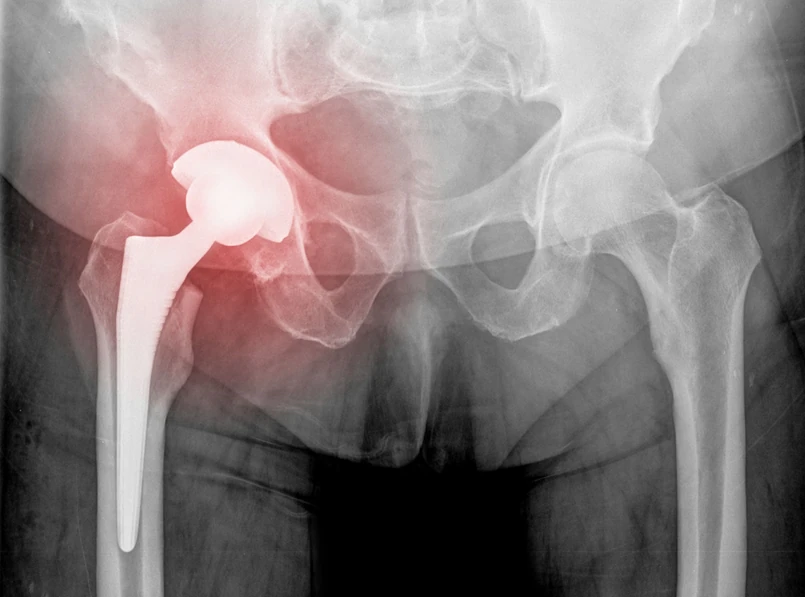

O ile w 2000 r. na leczenie złamań osteoporotycznych trzeba było przeznaczyć w Europie 1,7 mld euro, to w 2050 r. ta kwota może się zwiększyć do 76,7 mld euro. A do tego trzeba będzie jeszcze doliczyć koszty opieki poszpitalnej i długotrwałych zwolnień lekarskich. Nie wiadomo, ile takich złamań co roku jest w całej Polsce. Na podstawie danych Mazowieckiego Narodowego Funduszu Zdrowia ocenia się, że co roku może dochodzić do 28 tys. złamań szyjki kości udowej w naszym kraju.